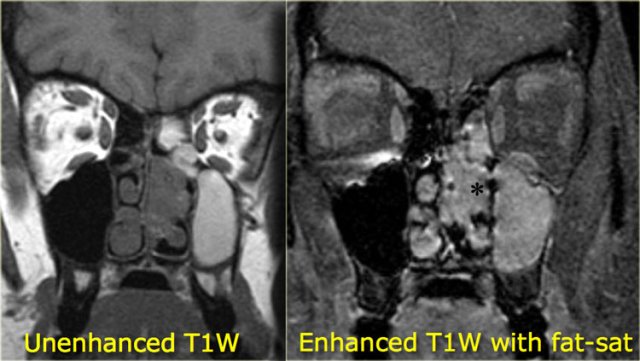

On the left an example of infectious sinonasal disease.

On the pre-contrast scan you see relatively high signal content of the maxillary sinusses due to proteineous material.

After the administration of i.v. contrast there is only enhancement of the circumferential mucosa and no solid enhancement.